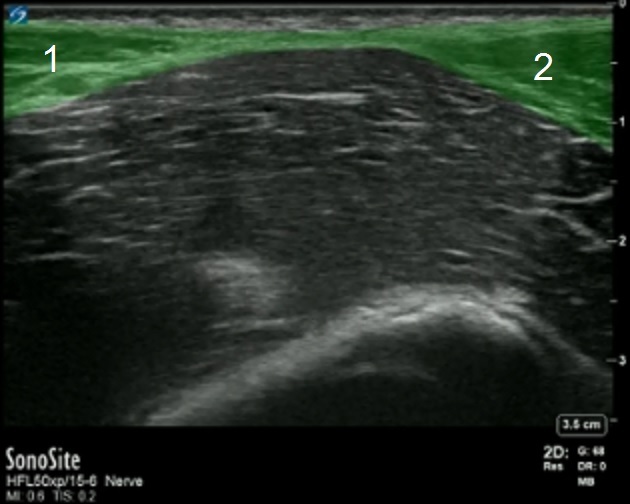

Lado izquierdo: Superior

Lado derecho: Inferior

1. Músculo oblicuo interno

2. Músculo sartorio